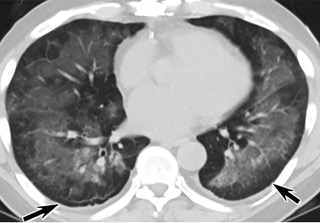

疑點(diǎn)一,電子煙患者的CT影像和臨床表現(xiàn)并不具有特異性。所謂美國(guó)電子肺炎患者,其實(shí)是對(duì)沒有其他合理診斷證據(jù)、吸食電子煙肺炎患者的統(tǒng)稱。這些患者在病發(fā)前90天內(nèi)吸食了電子煙,尤其值得注意的是,部分患者的CT影像特征和臨床表現(xiàn)與病毒性肺炎患者極其相似。

中、下肺軸位CT平掃顯示毛玻璃樣混濁伴胸膜下保留(箭頭)。(同一病人CT影像)